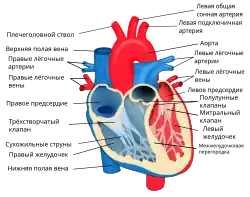

Сердце птиц и млекопитающих (зверей) — четырёхкамерное. Различают: правое предсердие, правый желудочек, левое предсердие и левый желудочек. Кровообращение: из одной или двух передних (верхних) и задней (нижней) полых вен кровь поступает в правое предсердие, затем в правый желудочек, затем по малому кругу кровообращения кровь проходит через лёгкие, где обогащается кислородом (оксигенируется), поступает в левое предсердие, затем в левый желудочек и, далее, в основную артерию организма — аорту (птицы имеют правую дугу аорты, млекопитающие — левую). Большой и малый круги кровообращения полностью разобщены.

Между предсердиями и желудочками находятся фиброзно-мышечные клапаны — справа трёхстворчатый (или трикуспидальный), слева двустворчатый (или митральный). На выходе из желудочков соединительнотканные клапаны (лёгочный справа и аортальный слева). Клапаны открываются только в сторону желудочков и поэтому пропускают кровь только в одном направлении: из предсердий в желудочки. Открываться в сторону предсердий створкам клапанов мешают сухожильные нити, отходящие от поверхности и краёв клапанов и прикрепляющиеся к мышечным выступам желудочков. Мышечные выступы, сокращаясь вместе с желудочками, натягивают сухожильные нити, чем препятствуют выворачиванию створок клапанов в сторону предсердий и обратному оттоку крови в предсердия.

Предсердия открываются в желудочки через атриовентрикулярные клапаны, присутствующие в межжелудочковой перегородке. Это различие видно также на поверхности сердца, как коронарная борозда. В верхнем правом предсердии имеется структура в виде уха, называемая придатком правого предсердия, или ушной раковиной, и ещё одна в верхнем левом предсердии — придаток левого предсердия. Правое предсердие и правый желудочек вместе иногда называют правым сердцем. Точно так же левое предсердие и левый желудочек называют левым сердцем. Желудочки отделены друг от друга межжелудочковой перегородкой, видимой на поверхности сердца в виде передней продольной борозды и задней межжелудочковой борозды.

Сердце человека состоит из четырёх камер, разделённых перегородками и клапанами. Кровь из верхней и нижней полой вены поступает в правое предсердие, проходит через трикуспидальный клапан (он состоит из трёх лепестков) в правый желудочек. Затем через лёгочный клапан и лёгочный ствол поступает в лёгочные артерии, идёт к лёгким, где происходит газообмен и возвращается к левому предсердию. Затем через митральный (двухстворчатый) клапан поступает в левый желудочек, затем проходит через аортальный клапан в аорту.

В правое предсердие входят полые, в левое предсердие — лёгочные вены. Из правого и левого желудочка выходят, соответственно, лёгочная артерия (лёгочный ствол) и восходящая аорта. Правый желудочек и левое предсердие замыкают малый круг кровообращения, левый желудочек и правое предсердие — большой круг. Сердце входит в состав органов среднего средостения, бо́льшая часть его передней поверхности прикрыта лёгкими. Со впадающими участками полых и лёгочных вен, а также выходящими аортой и лёгочным стволом оно покрыто сорочкой (сердечной сумкой или перикардом). В полости перикарда содержится небольшое количество серозной жидкости. У взрослого человека его объём и масса составляют в среднем для мужчин 783 см3 и 332 г, для женщин — 560 см3 и 253 г.